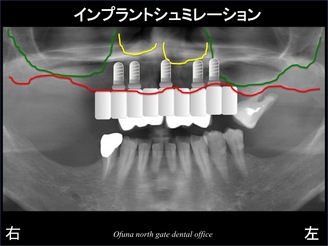

以下は、上下顎の欠損部全てにインプラントを埋入した場合のシュミレーションになります。

もし 上図のような治療になると骨移植 も必要になりますし、インプラントの本数もかなり多くなります。

この治療法は患者様のご希望ではありません。

そこで奥歯にはインプラントを埋入し

ない治療計画になりました。

下顎の奥歯の欠損部と上顎の奥歯の欠損部にはなにも行わない計画

です。

赤線の内側の範囲内でインプラントを埋入する計画になりました。

以下のシュミレーションが今回の治療方法になります。

奥歯にインプラントを行わない治療計画では、骨移植(上顎底挙上術) を行う必要性はありません。

また、インプラントの必要本数も最小限で行うことが可能です。

また、最も奥の部位には骨の吸収が大きかったため、同部位にはインプラントを埋入するために十分ではありませんでした。

そこでインプラントブリッジの最も奥の部位は、カンチレバー という方法で歯を作成する計画になりました。